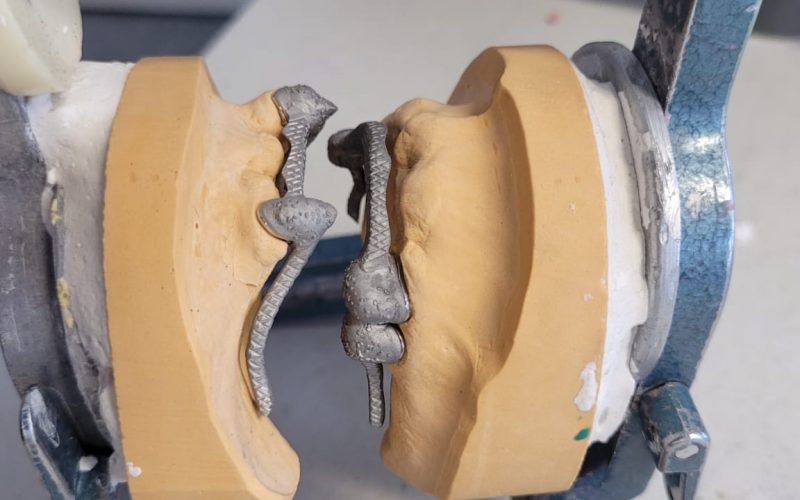

Telescope Crown & Attachment

Our precision-crafted telescope crowns and attachments provide excellent stability and durability, offering an ideal solution for patients requiring a reliable, long-lasting dental restoration.

Gallery

3D Laser Metal Printers for producing strong and intricate metal frameworks with exceptional precision.